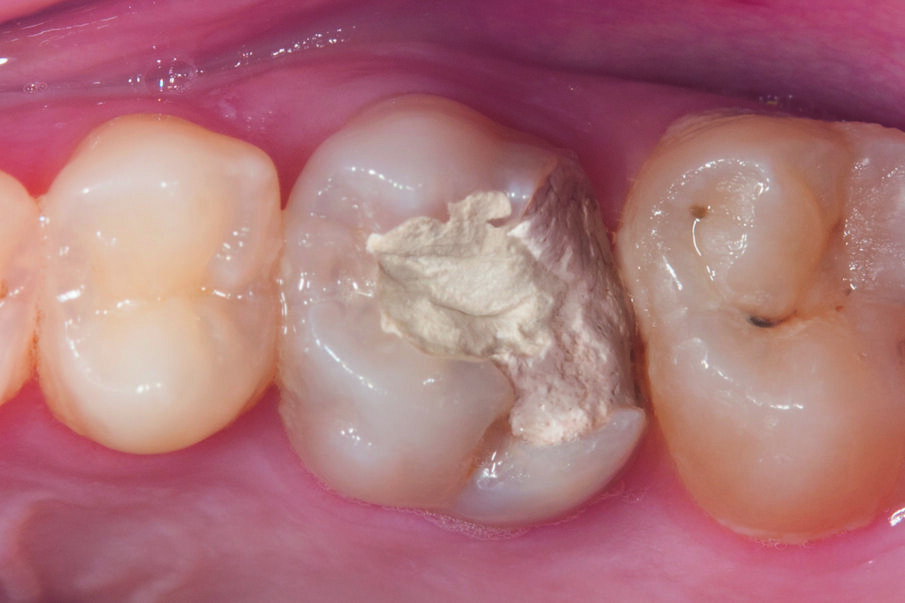

This case below shows a posterior tooth with an endodontic treatment followed by an indirect crown restoration. SDR® Plus is used as a core build up material before the crown was seated.

This case involves the use of SDR® Plus composite as a core build-up material. The outstanding flowability of SDR® Plus composite allows complete filling of the pulp cavity, even in the smallest recesses; the composite was placed in two stages to ensure thorough polymerisation. The periphery of the tooth was then prepared, preserving a layer of enamel at the preparation margin to ensure effective bonding of an all-ceramic crown. This was bonded with the Calibra® system. This protocol thus avoids iatrogenic mechanical strains on the tooth roots during core build-up. This treatment, involving a tooth/restoration monoblock with SDR® Plus composite and crown using only adhesive techniques, provides for outstanding biomechanical and aesthetic results.

Fig. 5: SDR® Plus first increment was light-cured for 20 sec, before a second layer of SDR® Plus was placed and light-cured.